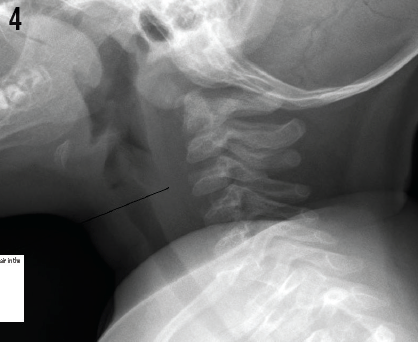

On day 3, chest radiographs (Figure 4) showed complete resolution of free air in the retropharyngeal space. The patient was discharged home that afternoon.